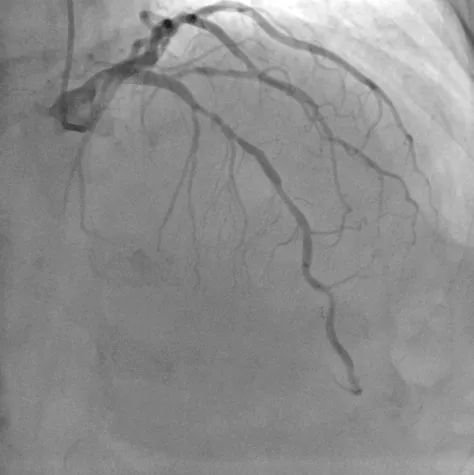

造影图:

造影显示提示前降支严重狭窄、回旋支次全闭塞、右冠慢性闭塞。

先后分期完成右冠及左冠PCI手术,但右冠CTO病变PCI手术术中出现开口夹层,一直撕裂至后三叉,且导丝位于假腔内。